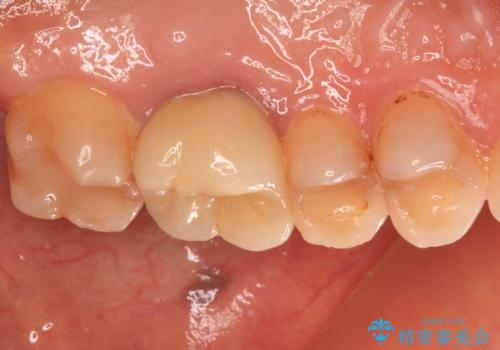

- 奥歯に装着したクラウンの周りに汚れが溜まりやすいとのことで来院された患者様です。

既に装着されているクラウンの質は決して悪いものではありませんでしたが、患者様自身が非常に気にしていたため、作り替えの治療を行うこととしました。

根管治療が必要と思えるような所見も認められませんでしたが、一緒に行いたいとの希望があったため、根管治療を行った上で補綴治療を行うこととしました。

クラウン装着後は、特にものが挟まる感覚もなく、快適に過ごすことができるようになりました。